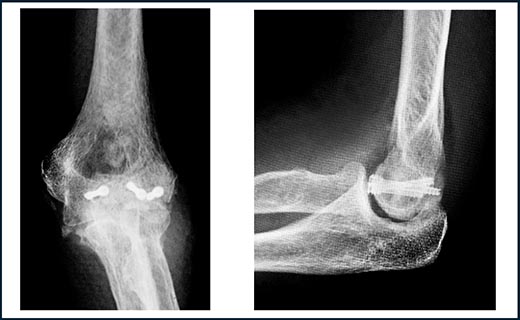

図7.上腕骨小頭・滑車骨折:スクリュー3本で骨片を固定しています。